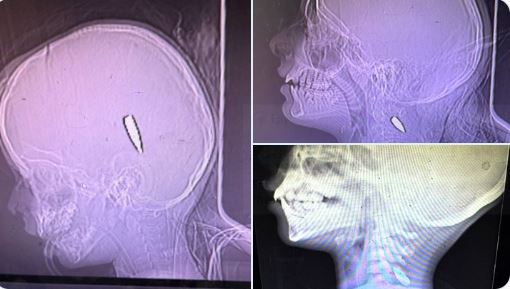

Ξένοι γιατροί στη Γάζα δημοσιεύουν ακτινογραφίες παιδιών που σκοτώθηκαν από Ισραηλινούς ελεύθερους σκοπευτές.

-τινάξτε τα μυαλά των παιδιών….